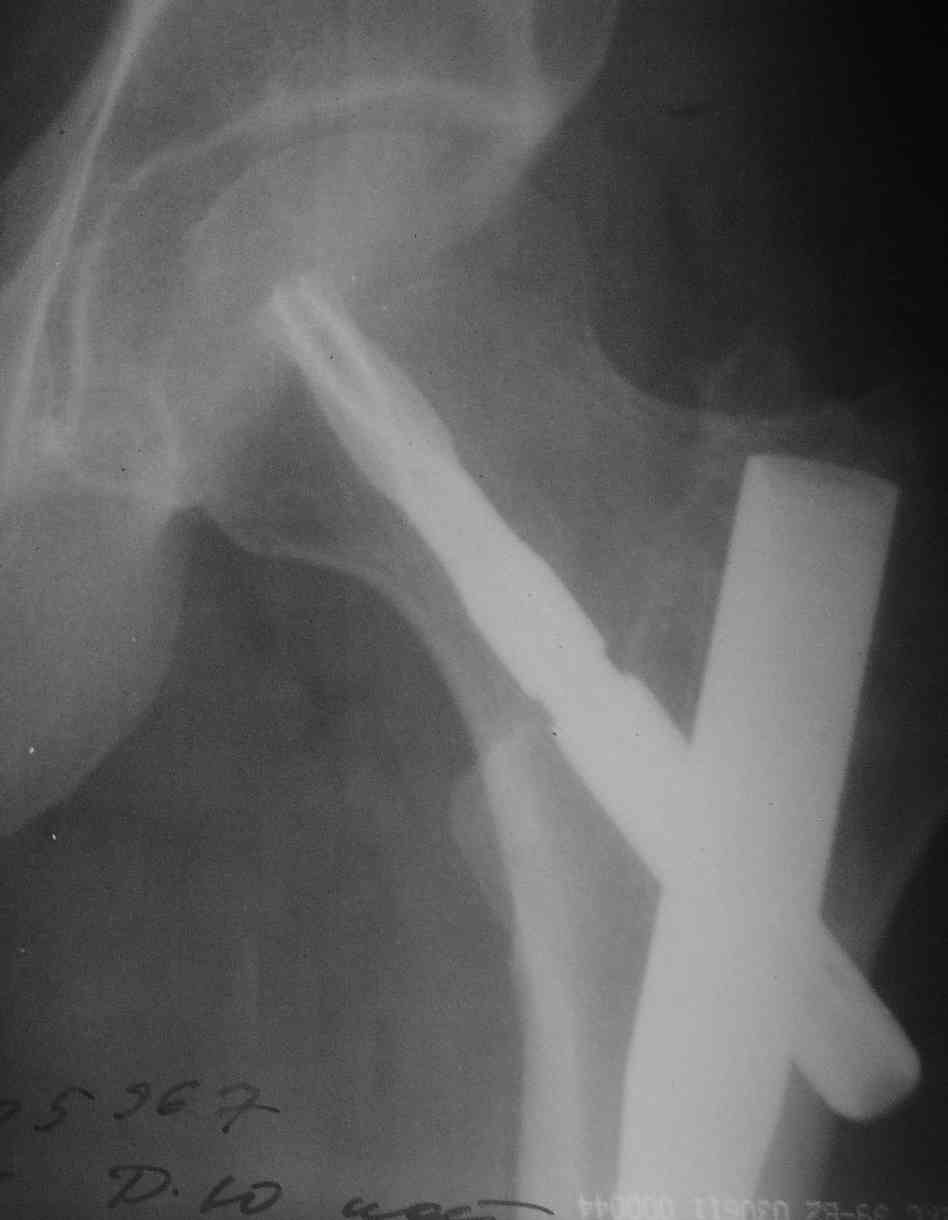

> Можно увидеть еще снимки: до , после....? Что за субъект?

Молодой мужик, была множественная травма. Снимок перед удалением вот.